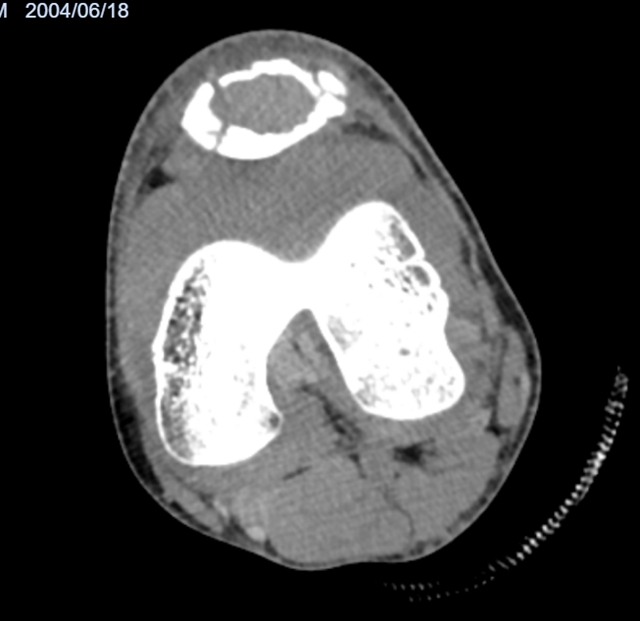

图1:术前的膝关节CT及磁共振检查,清晰显示髌骨肿瘤及病理性骨折

结合杨颖的情况和当地的检查结果,医生最终明确了问题:一是左侧髌骨因为肿瘤引发了病理性骨折,二是髌骨上确实长了骨肿瘤。